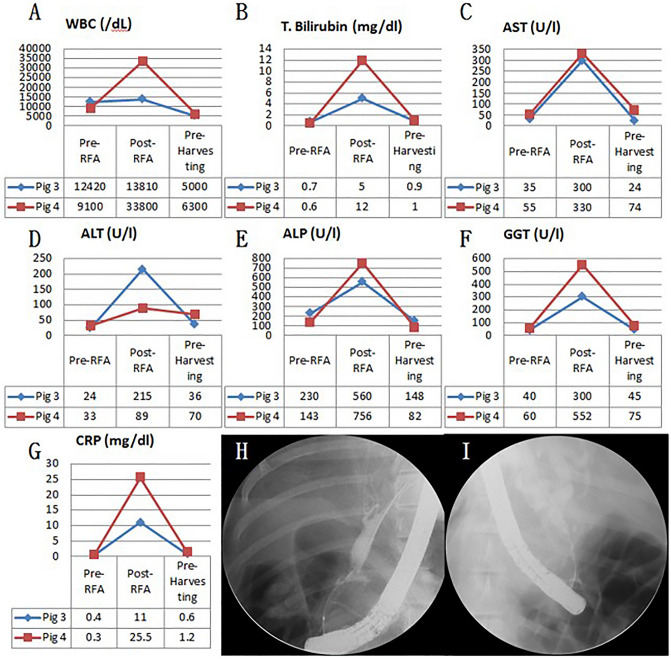

Fluoroscopic analysis via ERCP and blood analysis

In all six swine animal models, we succeeded in generating BSS using intraductal RFA without any complications such as bleeding or perforation (success rate = 100% (6/6), severe complication rate = 0%). Blood levels of WBC, AST, ALT, ALP, GGT, and CRP of all experimental animals were measured before the intraductal RFA procedure, after the intraductal RFA procedure (2 weeks after RFA), and before euthanizing animals (Figs. 1, 2, 3A–G). Blood levels of WBC, AST, ALT, ALP, GGT, and CRP were elevated after the intraductal RFA procedure but decreased after biliary stenting. Figure 1H,I are biliary fluoroscopy findings at 2 weeks after RFA in experimental animals 1 and 2, demonstrating biliary stenosis. The same trend of blood test results as in Fig. 1 was observed in Fig. 2. The difference between Figs. 1 and 2 was that the follow-up was performed at 3 months after biliary stenting in Fig. 2. Biliary stenosis was confirmed by fluoroscopy findings at 2 weeks after RFA in experimental animals 3 and 4 (Fig. 2H,I). Experimental animals 5 and 6 were followed for 5 months after biliary stenting. They showed the same tendency of blood test results (Fig. 3A–G). Biliary stenosis was also confirmed by fluoroscopy findings at 2 weeks after RFA in experimental animals 5 and 6 (Fig. 3H,I).